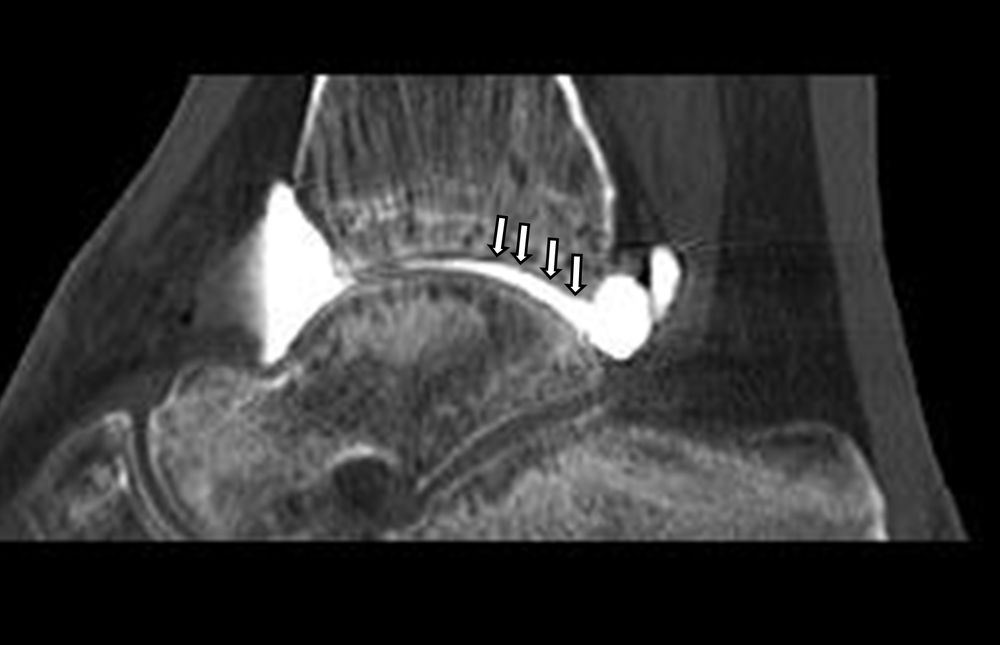

Είναι μια ελάχιστα επεμβατική απεικονιστική μέθοδος που επιτρέπει τη λεπτομερέστερη διερεύνηση του εσωτερικού των αρθρώσεων. Η ασφαλής έγχυση σκιαγραφικού εντός της άρθρωσης υπό ακτινολογική καθοδήγηση και η ακόλουθη απεικόνιση της άρθρωσης με αξονική ή μαγνητική τομογραφία (ή και με συνδυασμό των μεθόδων) αποσαφηνίζει βλάβες του χόνδρου και κακώσεις-ρήξεις συνδέσμων και τενόντων με υψηλή ακρίβεια, συμβάλλοντας σημαντικά στο λεπτομερή χειρουργικό σχεδιασμό.